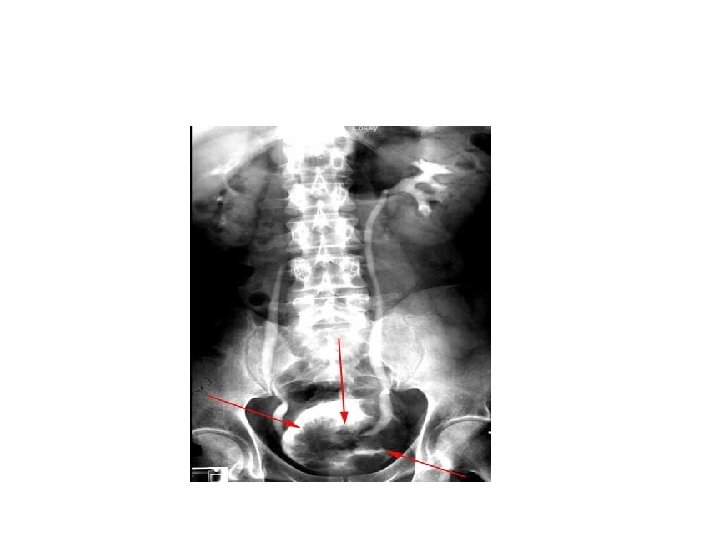

• Occupational exposure: like rubber or gas manufacture, painters, hairdressers • Drugs: phenacitin(acetaminophen) commonly used antipyretic and analgesic, cyclophosphamide( chemotherapy) • Pelvic radiotherapy • Chronic inflammation: longstanding catheter, bladder stone , schistosoma hematobium are associated with SCC of bladder

ultrasound